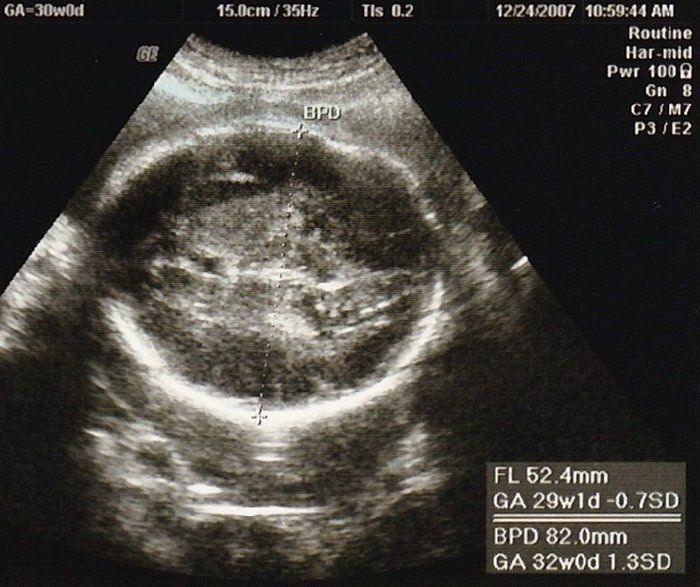

こぢんまり子さんの妊娠30週目のエコー写真 赤ちゃんの体重が少なめだと指摘される

エコーは左下の曲線が頭、真ん中の白っぽいのが手です。おなかの中で、よくしゃっくりをする赤ちゃんでした。しゃっくりをしているときにおなかに触ると、びくっとしているのが分かるので、夫にも触ってもらい、2人で「元気だね」と喜びました。

検診ではエコーで赤ちゃんの太ももの長さと頭の長さを計測して、推定体重を教えてもらっていたのですが、この頃から赤ちゃんの体重が少なめだと医師に言われるようになりました。